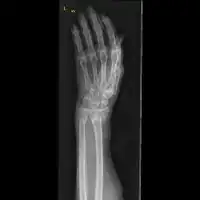

![]() | |

| Midshaft fracture of the radius and ulna | |